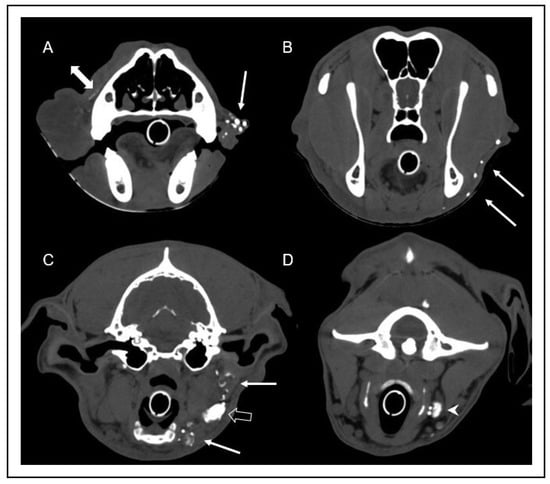

Figure 4. Transverse computed tomography images after intravenous contrast media injection in soft tissue window at the level of the mid nasal cavity (A), the frontal sinus and mandibular ramus (B), and the tympanic bulla (C). Note the marked low attenuation swelling consistent with subcutaneous edema (arrow) of the right lip (A) and neck (B), extending caudoventrally to the region of the mandibular lymph nodes (C). In image (C), the hypoplasia of the right mandibular lymph nodes (arrowhead) can be appreciated in comparison to the left mandibular lymph nodes (open arrows).

The CT of the head, neck, and thorax revealed marked diffuse subcutaneous low-attenuation swelling of the right upper lip and cheek, extending caudally to the laryngeal region, where subcutaneous fat stranding was identified. The main finding was a small right mandibular lymph node (3.5 mm in height) compared to the left side (10 mm in height). The size of all other lymph nodes was considered appropriate for the patient’s age and symmetry.

Immediately after injection, multiple lymphatic vessels were visualized on the left side, draining to the ipsilateral mandibular and medial retropharyngeal lymph nodes. On the right side, a scant volume of contrast media was identified, extending caudally from the injection site along the facial planes. No lymphatic vessels or lymph node enhancement could be appreciated on the right side in any scan (Figure 4 and Figure 5). In summary, there was absent lymphatic drainage of the right upper lip/cheek, and the small right mandibular lymph nodes were considered to be hypoplastic. In light of these findings, the most likely diagnosis was a primary lymphedema due to absent or malfunctioning lymphatic vessels.